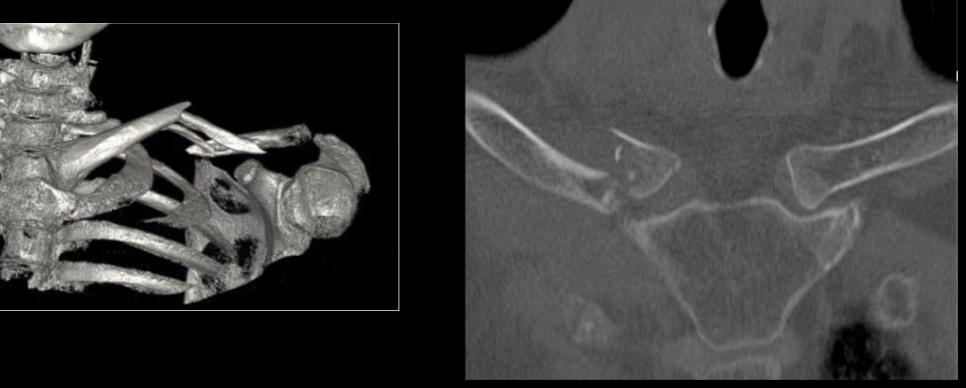

A

Fx clavicula

TC fx clavicula